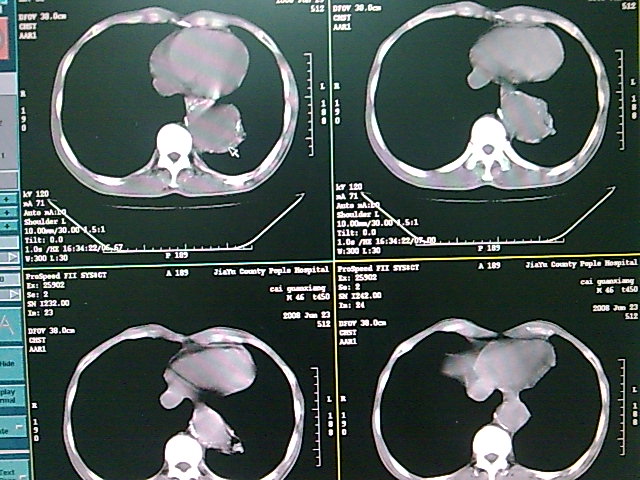

以下是引用dyqct在2008-6-27 14:37:00的发言:[br]支持胸主动脉瘤,建议增强进一步检查。

以下是引用zsl6918在2008-6-27 14:24:00的发言:[br]动脉瘤